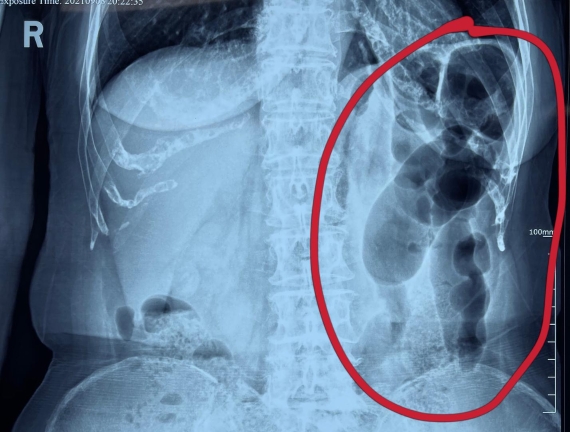

據(jù)省醫(yī)院消化病院消化二科姜子曄醫(yī)生介紹,韓大娘今年已經(jīng)73歲,家住哈爾濱市,一周前開始腹脹腹痛,有較為明顯的左側(cè)腹部疼痛,疼痛劇烈時(shí)會(huì)出現(xiàn)左側(cè)腹部鼓包情況,排氣排便后有所好轉(zhuǎn)。韓大娘家人見狀將其送到了黑龍江省醫(yī)院,門診檢查腹部平片提示為左側(cè)腹部積氣,口服全消化動(dòng)力藥及通便治療后腹痛腹脹有所緩解,入院前再次突發(fā)左側(cè)腹痛加重伴有明顯腹脹,急診隨后以“腹痛腹脹原因待查”將韓大娘收入到消化病院消化二科。

姜子曄醫(yī)生熱情接待了韓大娘,為其進(jìn)行了仔細(xì)查體,除了左側(cè)腹部壓痛并未見明顯異常,對(duì)癥給予灌腸后,韓大娘的腹脹有所緩解,第二天姜子曄醫(yī)生為韓女士進(jìn)行了胃腸鏡檢查,也未見明顯異常。但此時(shí)韓大娘腹部平片結(jié)腸腸管擴(kuò)張仍然很嚴(yán)重,腹痛腹痛也沒緩解,到底什么原因呢?消化二科主任陸以霞在查房時(shí)建議繼續(xù)給予韓大娘口服全消化動(dòng)力藥,必要時(shí)灌腸治療,同時(shí)陸以霞主任在追問(wèn)病史查體時(shí)發(fā)現(xiàn)韓大娘左下腹紅色皮疹和小水泡,反復(fù)抓撓腹部皮膚部分已結(jié)痂,高度懷疑為帶狀皰疹。